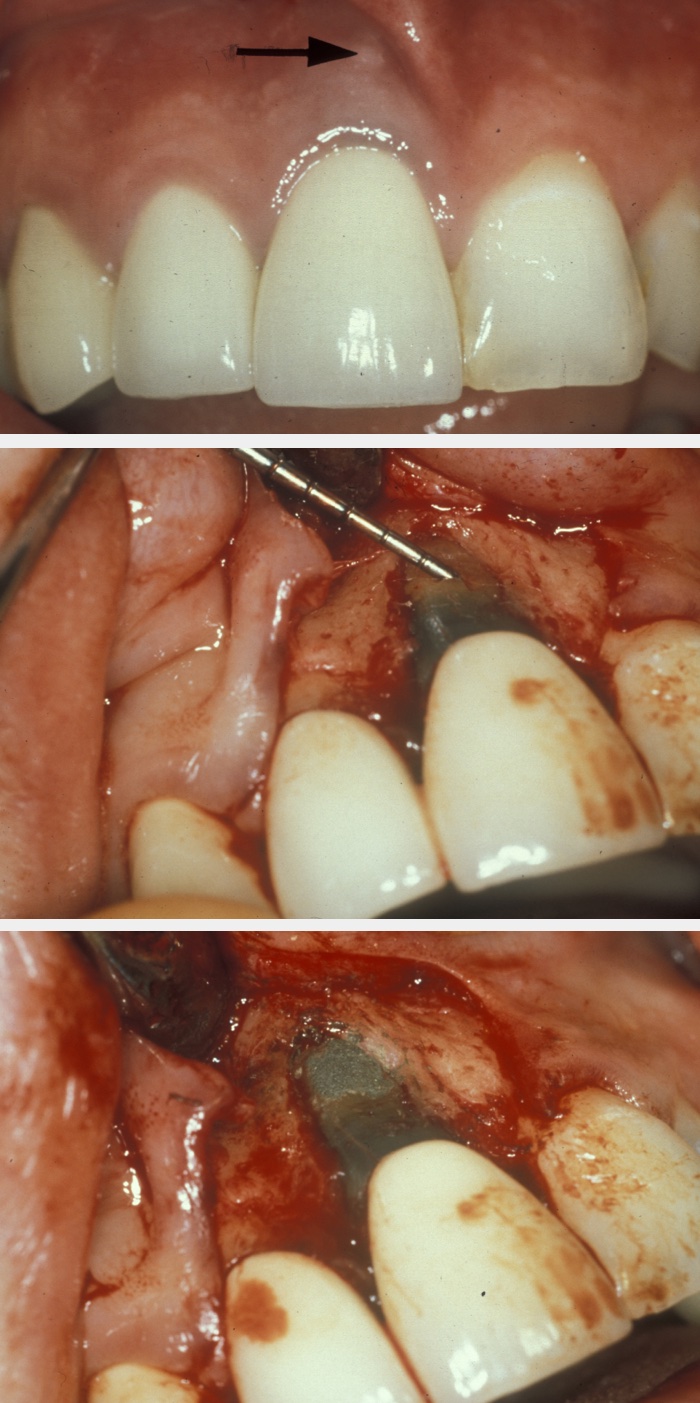

Perforation repair becomes necessary to deal with root perforations caused by broken endodontic instruments or damage by posts, and resorption cavities. If the prognosis of the tooth is acceptable, surgical access is gained to the site of the perforation, the area is prepared and then filled with, for example, mineral trioxide aggregate. Figure 1 illustrates an example; the apparent over-bevelling is a consequence of this being a perforation repair and not a conventional apicectomy.